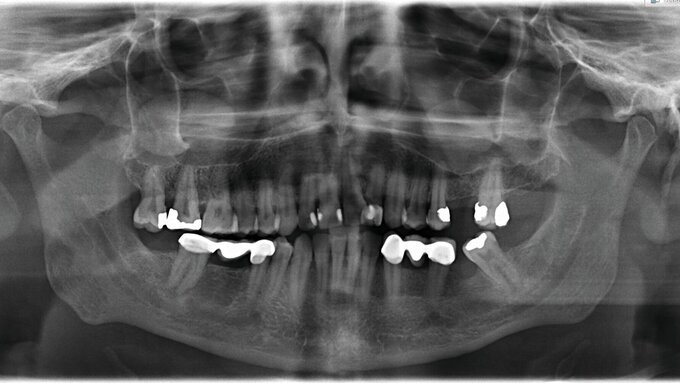

Nach Anfertigung einer Panoramaschichtaufnahme bestand der Verdacht auf das Vorliegen einer Zyste. Zur genaueren dreidimensionalen Diagnostik wurde eine native Computertomografie veranlasst. Im Übergangsbereich des linken Nasenvorhofs zur Nasenhaupthöhle imponierte eine runde, homogene Verschattung, die die Apertura pririformis im dorsalen Anteil erodierte und den Alveolarfortsatz nach palatinal bis zu den Wurzelspitzen der Zähne 21 bis 24 verdrängte (Abbildung 1). Daraufhin wurde die Indikation zur Zystektomie gestellt.